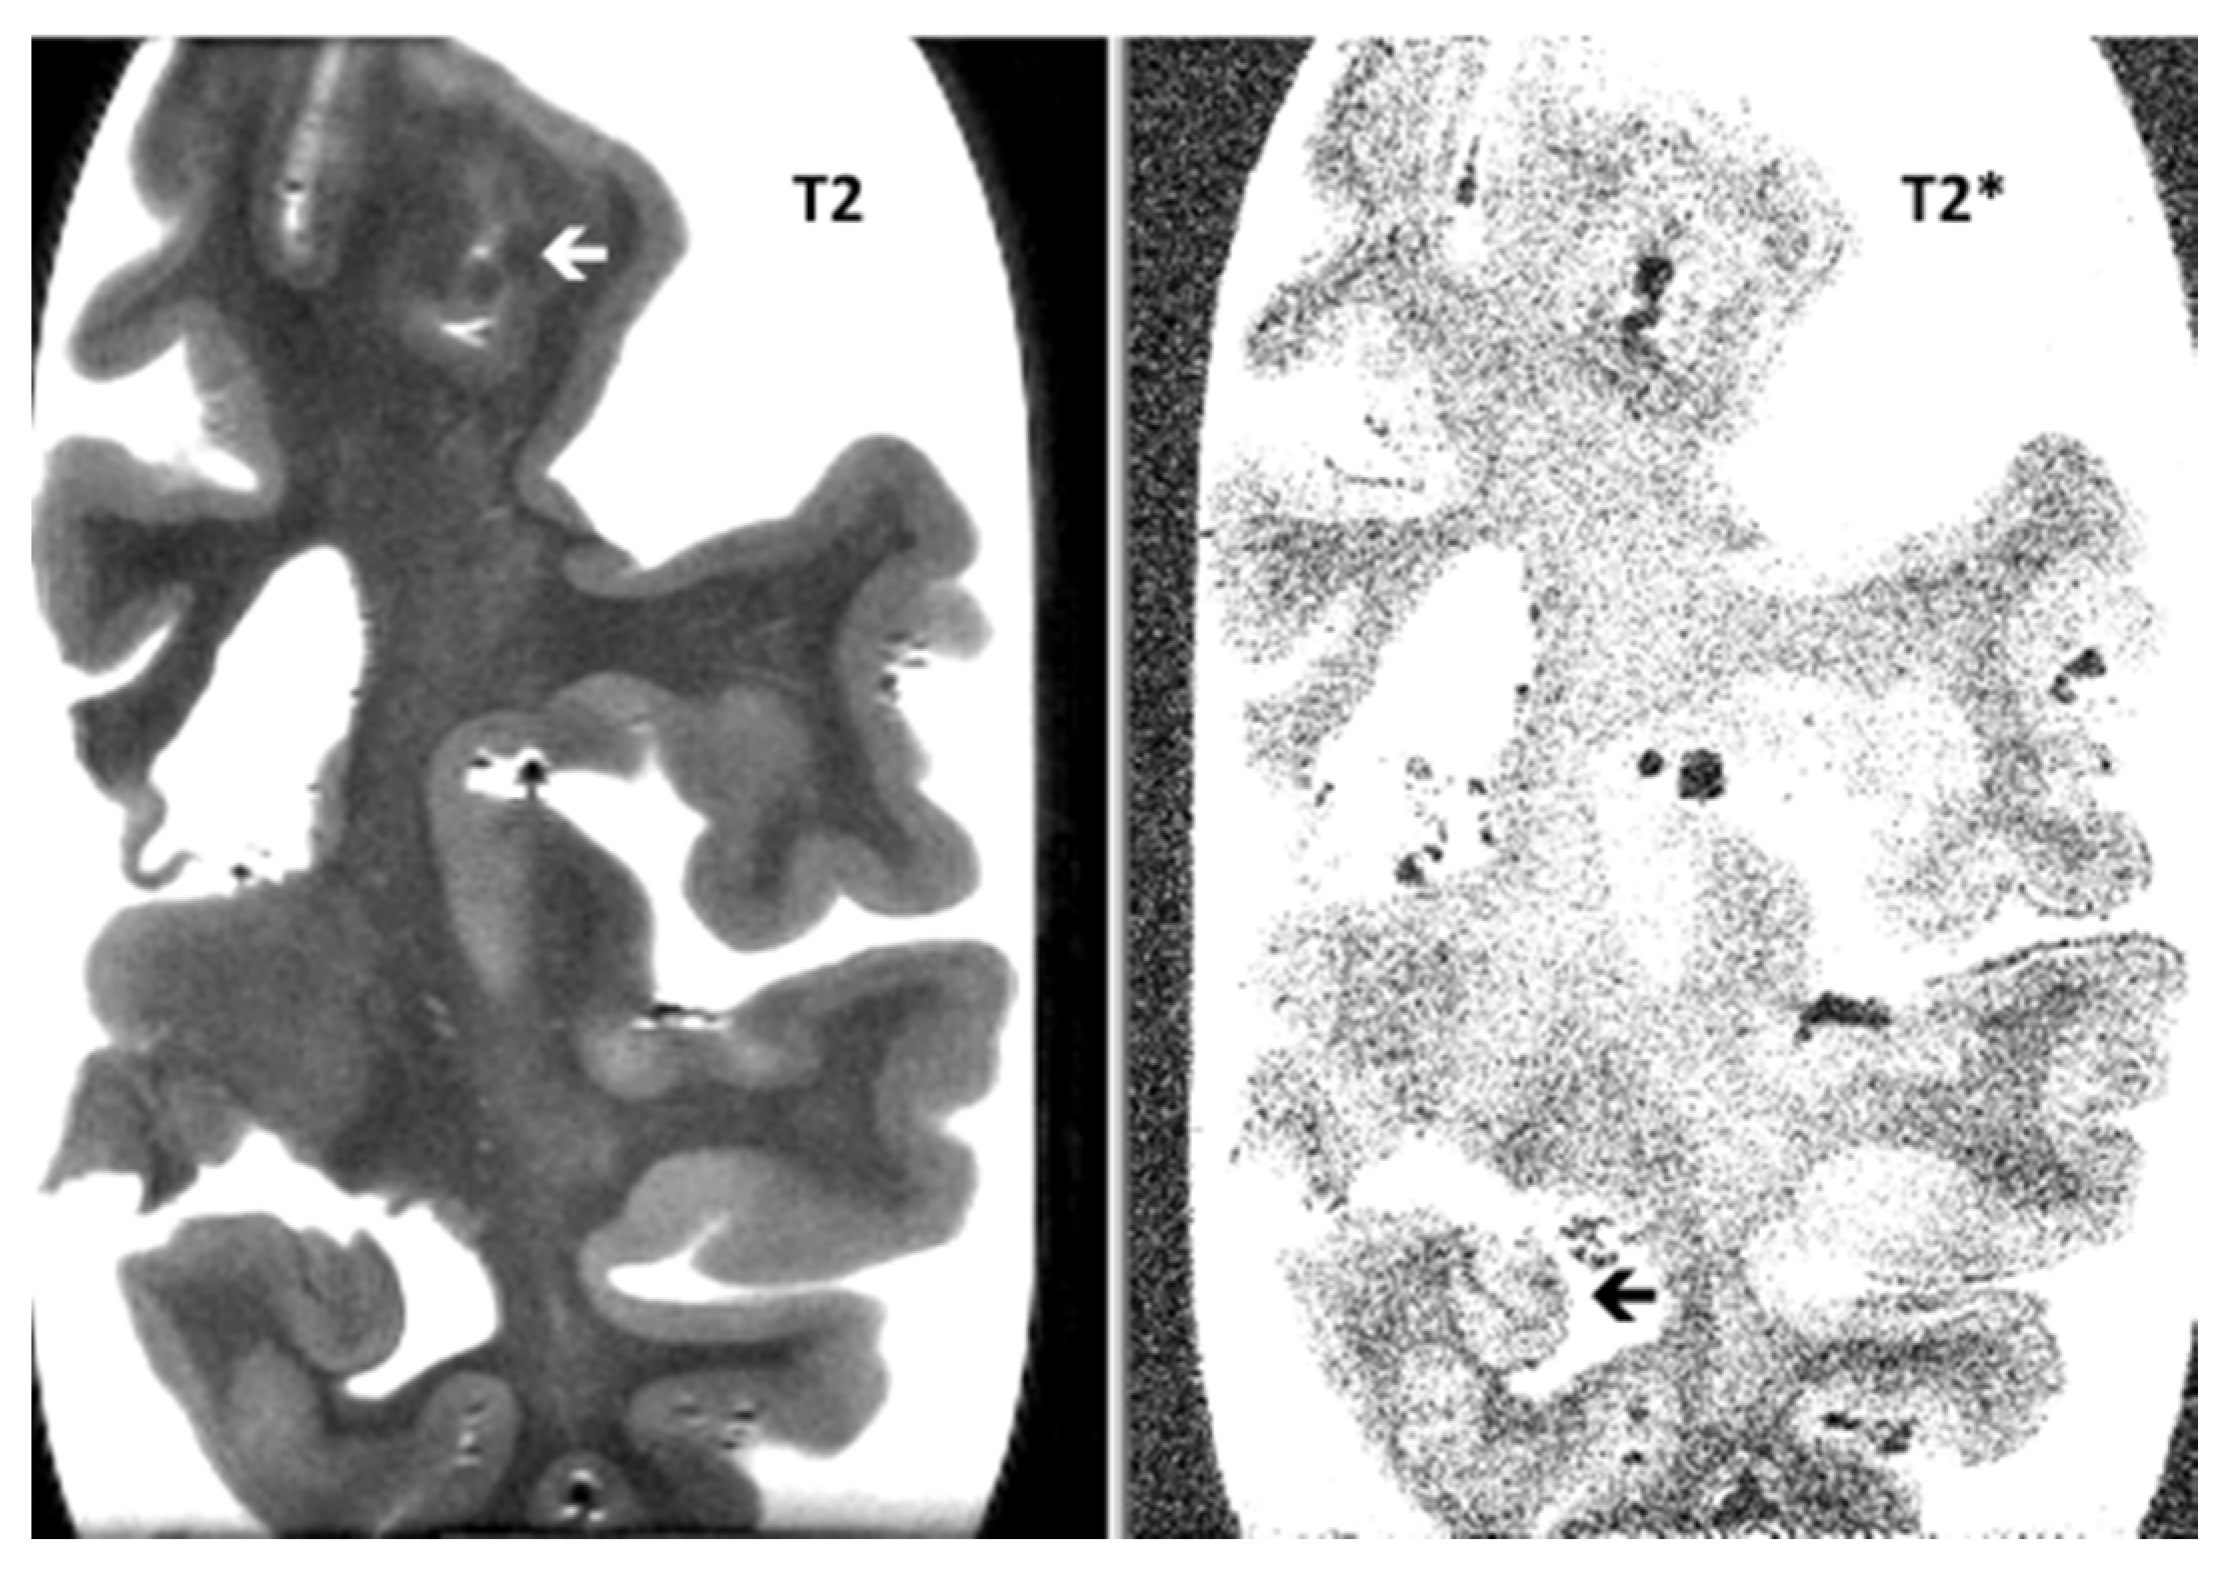

Post-Mortem 7.0-Tesla Magnetic Resonance Imaging of the Hippocampus in Progressive Supranuclear Palsy with and without Cerebral Amyloid Angiopathy

3. Results

| Hippocampal micro-bleeds | 0.9 (0.6) | 0.4 (0.5) | NS |